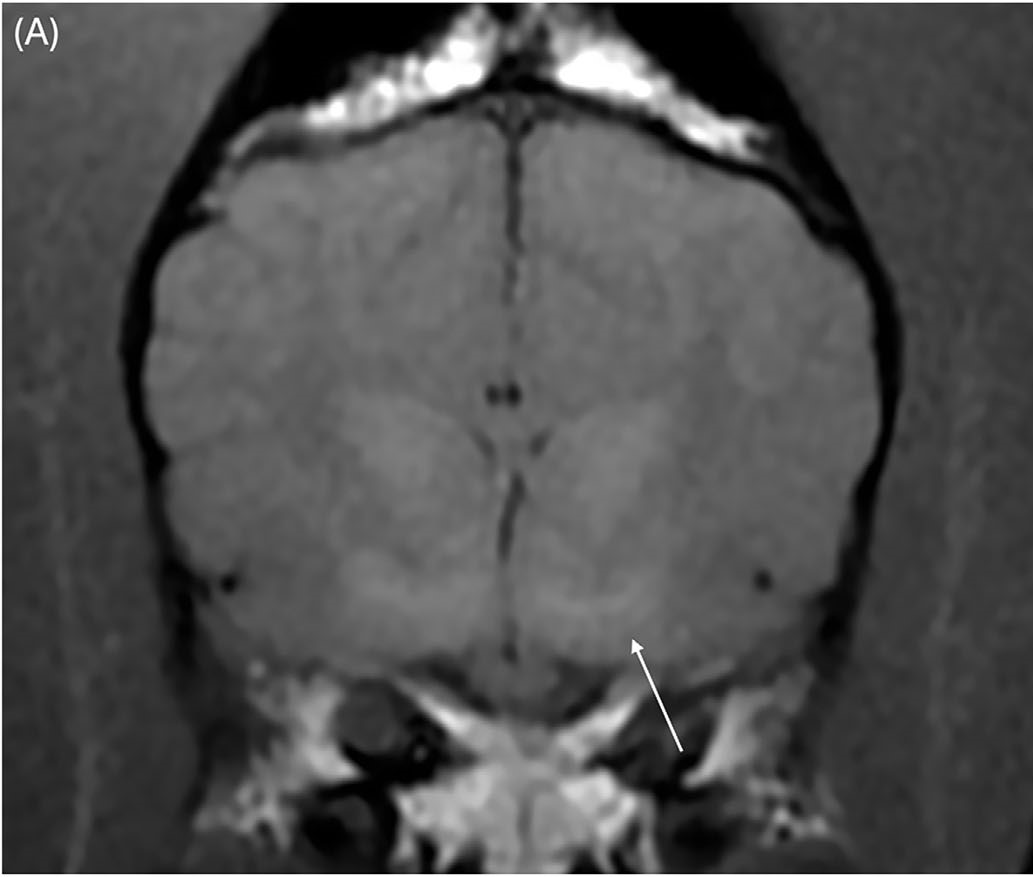

颈椎MRI图像大多未见异常,仅显示颈椎间盘纤维环的轻度非压迫性突出。脑部成像显示双侧对称、边界不清的T2和T2-FLAIR高信号,影响丘脑(图1A)、内侧和外侧膝状体(图2A)、导水管周围灰质和红核(图2A)。在双侧豆状核(图3A)、丘脑(图1B)和膝状核(图2B)内可见T1高信号。这些病变未显示对比增强。未在任何可见的骨或软组织结构中发现异常。

图3.(A)豆状核(白色箭头)中可见双侧对称、边界不清的T1高信号。

与治疗前相比,先前注意到的T2和T2-FLAIR高信号区域都有显著改善。在丘脑(图4C)、内侧和外侧膝状体以及红核中仅见非常轻微的双侧对称、边界不清的T2高信号(图5C)。先前注意到的豆状核中的T1高信号区域已完全消失(图6B)。

图6.(B)横断面T1加权图像显示,在铜螯合治疗开始7个月后,豆状核中的双侧病变已完全消失。